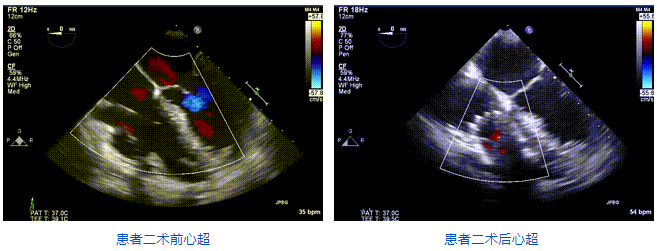

本周三例接受LuX-Valve Plus經(jīng)血管三尖瓣置換術(shù)的患者中,第一例患者為冠狀動(dòng)脈旁路移植術(shù)+Bentall+二尖瓣成形術(shù)后;第二例患者為永久起搏器植入術(shù)后,存在跨三尖瓣導(dǎo)線;第三例患者合并房顫、房缺及左心耳封堵術(shù)后。

三例患者入院后,葛均波院士團(tuán)隊(duì)周達(dá)新教授、潘文志教授、張?jiān)床┦?、陳莎莎博士及心超室的潘翠珍教授、李偉教授?duì)患者的情況進(jìn)行詳細(xì)評(píng)估和討論,最終決定為三例患者選擇LuX-Valve Plus40mm、50mm和50mm型號(hào)的瓣膜進(jìn)行手術(shù)治療。手術(shù)后即刻拔除氣管插管,術(shù)后患者三尖瓣反流癥狀得到顯著改善,復(fù)查心超結(jié)果顯示人工三尖瓣瓣膜支架固定穩(wěn)定,瓣葉關(guān)閉形態(tài)未見異常,未見明顯反流。